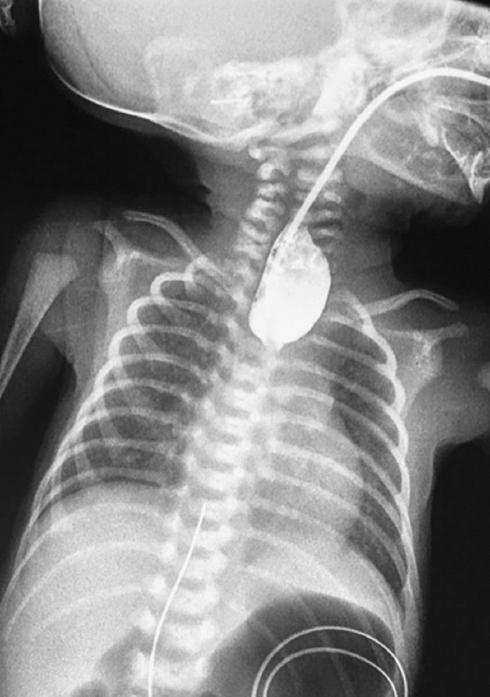

La atresia de esófago se observa en un alto porcentaje de nacimientos prematuros o de neonatos con peso bajo al nacimiento5. Los pacientes que se ven afectados por esta patología permanecerán asintomáticos en las primeras horas, pero luego mostrarán sialorrea, dificultad respiratoria, tos y ahogamiento al momento de la alimentación. Si el diagnóstico se realiza de forma tardía puede presentarse un proceso neumónico grave que ensombrece el pronóstico4-6. El diagnóstico se corrobora mediante radiografías de tórax y de cuello, tanto anteroposteriores como laterales, colocando una sonda radioopaca o bien un medio de contraste hidrosoluble (Fig. 1). Si hay una fístula traqueoesofágica distal, el aire en el estómago estará presente en las radiografías y la distensión abdominal puede ser evidente4,5,14.